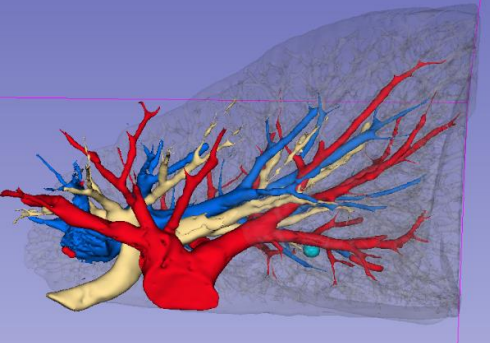

随着大众对健康的重视,肺CT扫描筛查的人群越来越多,许多的肺小结节被发现。CT发现有肺小结节后患者往往非常恐慌,那么如果发现有肺小结节究竟该怎么办? 临床上将CT检查显示的肺部直径小于 30mm的类圆形或者不规则密度增高阴影称为肺结节。而如果直径小于20mm习惯上称肺小结节,直径小于5mm,称微小结节。CT显示结节有的密度很高或者有钙化,有的显示为纯磨玻璃样阴影,有的则显示为混杂磨玻璃样结节。 当发现肺上有结节之后,自然想知道肺结节是良性还是恶性,下一步就是怎么治疗。患者可能会去很多医院就诊,网上搜索相关知识,得到的回答可能各不相同。有的认为肺结节是肺癌可能性很小,建议观察随访。有的建议手术,有的建议穿刺检查。患者究竟该听取那个医生的建议呢?这是一个很复杂的问题,既然医生给出不同建议、没有确定方案,就说明有很多问题需要进一步研究。 最具权威性的NCCN指南推荐:直径 8mm以下观察,8mm以上可以考虑手术。但肺结节的诊疗方案真的就如指南这样简单吗?肺小结节的诊断及治疗牵涉很多因素,手术能够完全治愈肺癌。如果肺小结节是肺癌,肯定越早手术越好,因此肺小结节患者的选择其实就是随访观察或者手术。 那也有患者会问,手术前可不可以穿刺明确诊断呢? 穿刺有两种结果,找到癌细胞和没找到。但如果没找到,也不能排除是肺癌的可能,还是需要手术;找到了,那肯定更需要手术,所以穿刺对需要手术的患者,没有价值。相反,穿刺肯定会刺破肿瘤的基膜,可能造成癌细胞种植、血液及淋巴结管播散,让本来是早期的肺癌变成晚期。 虽然有文章报道肺小结节是肺癌的可能性很小,但是在我们医院经我们会诊后手术的肺小结节患者,90%都是肺癌。因此发现肺部结节千万不能大意,一定要去正规的三甲医院,尤其是肿瘤医院的胸外科就诊,听取专家意见。 究竟是观察或者手术,以下因素需要综合考虑。 CT提示结节较大,直径超过8mm,即使高度怀疑肺癌的结节,最少还是可以观察2周时间,看结节会不会缩小或者消失,然后才考虑是否需要手术。 如果结节很小,直径小于5mm,大部分都可以长期随访观察,除非结节形态高度怀疑肺癌,经随访结节持续存在,甚至有微小变化,可以考虑手术切除。 如果CT发现增值病灶或者有钙化灶,一般会建议随访,考虑良性可能性大。这种情况建议每年复查CT就可以。 纯磨玻璃结节直径小的可以随访,半年或者一年随访一次胸部CT。较大的考虑原位腺癌,原位癌不会发生转移,所以随访时间长也不用太担心。 混杂样磨玻璃结节尤其是实性成分占多数的,这种情况肺癌可能性显著增加, 而且会有癌细胞侵润,不适合长时间随访,应该尽早手术,即使结节直径小于8mm。 结节的位置对于制定诊疗计划也很重要。左右各侧肺分为上肺叶、中(舌肺叶)及下肺叶。每个肺叶又由很多肺段组成。 建议长期观察随访的肺结节,我们会根据病灶位置及大小形态来建议观察随访间隔时间长短。如果结节靠近肺门,考虑肺癌可能,会建议密切观察,3个月做一次CT。因为靠近肺门的结节,一旦增大,手术切除就比较困难,而且容易发生肺门淋巴结转移。随访间隔时间长,肿瘤增大较快,由于靠近肺门,可能造成肿块边缘距离正常组织的切缘不够,肿瘤容易复发甚至不能完全切除。 靠近肺周边的结节,尤其是靠近胸膜的肺结节,经过一段时间随访,如果结节形态像肺癌,可以积极手术切除。理由是: 1.靠近胸膜结节容易转移,胸膜种植; 2.对周边肺结节切除肺组织相对少,对患者肺功能影响很小。 图1 肺结节位于肺实质较深的位置 如果肺结节位于肺实质较深的位置(图 1),但在肺段的中间,可以行肺段切除,这种情况也可以相对积极手术。但是如果结节位置较深,同时位于几个段交界处,又不适合亚肺段切除,则可以继续观察,在结节继续增大或者出现部分实性成分,再考虑肺叶切除。 肺功能也是制定手术方案时需要考虑的因素。有的患者肺功能较差,只能承受肺段或者楔形切除手术,甚至不能手术,这种情况我们在确诊后可以考虑射频消融及术后辅助治疗。对于多个肺结节,需要切除较多肺组织,而肺功能不容许,可以切除部分表浅的肺结节,对深部的结节射频消融。这部分患者术后需要化疗及靶向治疗。 胸腔镜手术应用已经很普及了,手术创伤小,患者恢复快。我们开展的单孔腔镜手术(图2),创伤更小,一个3cm 小孔,可以完成肺部各种手术。如果没有掌握单孔腔镜技术,尤其是有的医生甚至还要开胸撑开肋骨创伤较大的手术方式,对肺结节的手术,可以更保守一点,随访时间更长,确诊后再手术。 图2 单孔腔镜手术 肺结节的治疗,医院设备条件也是非常重要。除了手术设备,更重要的是肺结节定位设备。由于我们开展的单孔腔镜手术,对磨玻璃结节用指头去触摸很困难,而且不准确。有的部位手指到达不,因此就需要一些设备方法在手术前及手术中对肺结节的精确定位。 图3 三维成像技术 三维成像技术(图3)在临床中使用最广,因为对设备需要不高,只要一台电脑,下载mimics软件,就能对肺结节定位和规划手术。这其实就是将薄层CT 图像整合成三维图形,便于更直观的观察解剖位置及与支气管及血管的关系。但是这种技术定位肺结节有很大局限性。CT是在肺膨胀时候采集的图形,因此做出的三维图像是肺膨胀时的图像,而我们在手术中肺是萎陷的,肺缩小很多,和膨胀时差别很大。如果肺结节刚好在段的中间位置,做肺段切除借助三维成像很有帮助。但是如果结节在几个段交界或者靠近段边缘,手术有可能漏掉结节,或者把结节切碎,导致肺癌复发。 目前更先进的设备有肺结节导航系统,包括磁导航和更先进LUNG-pro导航技术(图4)。可以对肺深部的结节定位,注射染色剂或者放置标记物定位。 图4 肺结节导航系统 手术室中的移动CT(图5),可以让手术变得更简单。重庆大学附属肿瘤医院复合手术室配备有移动CT,患者麻醉之后摆好手术体位再用定位针定位,患者处于麻醉状态,定位更准确,患者没有恐惧感觉,而且没有风险。 图5 重庆大学附属肿瘤医院复合手术室中的移动CT 手术切除肺段时需要判断肺段间的界面,大多数医院都是采用膨胀萎陷法。不过由于有的患者有肺气肿,手术中肺萎陷不好,这种方法就不适用。重庆大学附属肿瘤医院的荧光腔镜(图7)可以精确定位肺段界面,当相应的肺段动脉切断后,静脉注射吲哚青绿,要切除的肺段就不会显示染色。这种方法准确,也缩短了手术时间,又能最精确手术。 肺小结节是观察还是手术,不是只看大小及有无实性成分,更要根据每个患者的个体情况,考虑到各种因素,力求个体化的治疗方案。为了达到精准治疗肺小结节,重庆大学附属肿瘤医院胸部肿瘤中心全科室医生均采用单孔的肺结节手术,中心配备了全球最先进的设备,综合实力全球领先。时刻为了患者的健康保驾护航。